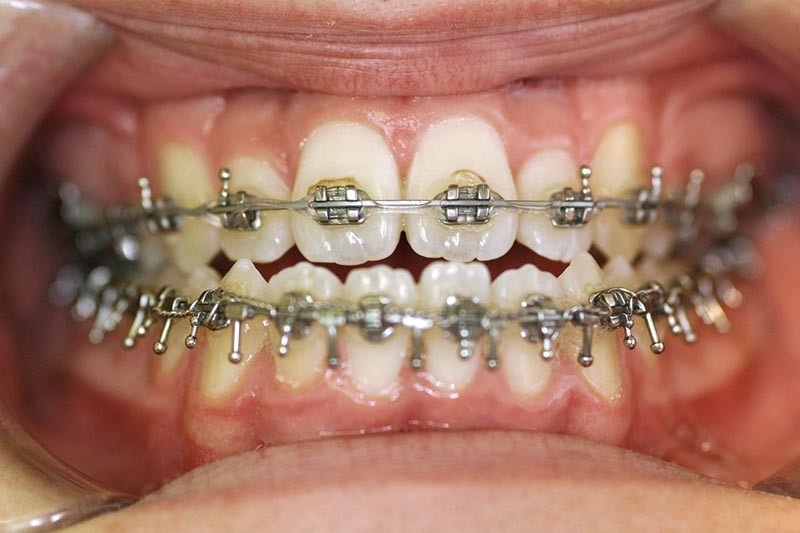

Olivier se présente à l’âge de 12 ans avec une classe III squelettique à prédominance mandibulaire, accompagnée d’une hyperdivergence et d’une endomaxillie responsable des inclusions des canines supérieures à forte obliquité. Une phase d’expansion est réalisée afin de permettre une augmentation du périmètre de l’arcade et la verticalisation des germes des canines. L’expansion permet en effet une normalisation transversale mais ne permet pas de réaliser la mise en place des canines. Les extractions des prémolaires sont alors effectuées et une préparation primaire de l’arcade supérieure par multi-attaches avec désinclusions et tractions des canines est réalisée.

Une pause thérapeutique est ensuite entamée jusqu’à la fin de croissance soit 18 ans. Une poursuite du traitement par préparation secondaire à la chirurgie orthognathique bimaxillaire est programmée.

Les mouvements de décompensations sagittales et transversales sont réalisés à l’aide des tractions inter-arcades. La réévaluation céphalométrique et l’analyse des moulages confirment l’indication d’une chirurgie maxillaire de propulsion et d’une chirurgie mandibulaire par clivage bilatéral des branches montantes pour un recul mandibulaire modéré accompagné d’une génioplastie bidimensionnelle élargie qui rappelle la technique de Chin Wing.